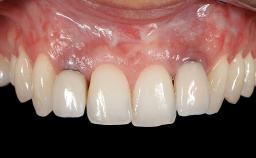

Treatment of Soft-Tissue Fenestration in the Esthetic Zone

This case demonstrates that a connective-tissue graft in combination with a coronally positioned graft is an effective method of treating cases with peri-implant mucositis and an abutment-level sinus abscess. A 42-year-old man presented with a swelling adjacent to an implant crown at site 21. The swelling had been present for approximately three weeks and was constrained to the buccal and palatal gingival aspects of the implant. A discharge was noted on finger pressure, with localized gingival recession present on the mid- and distolabial aspects of the crown.